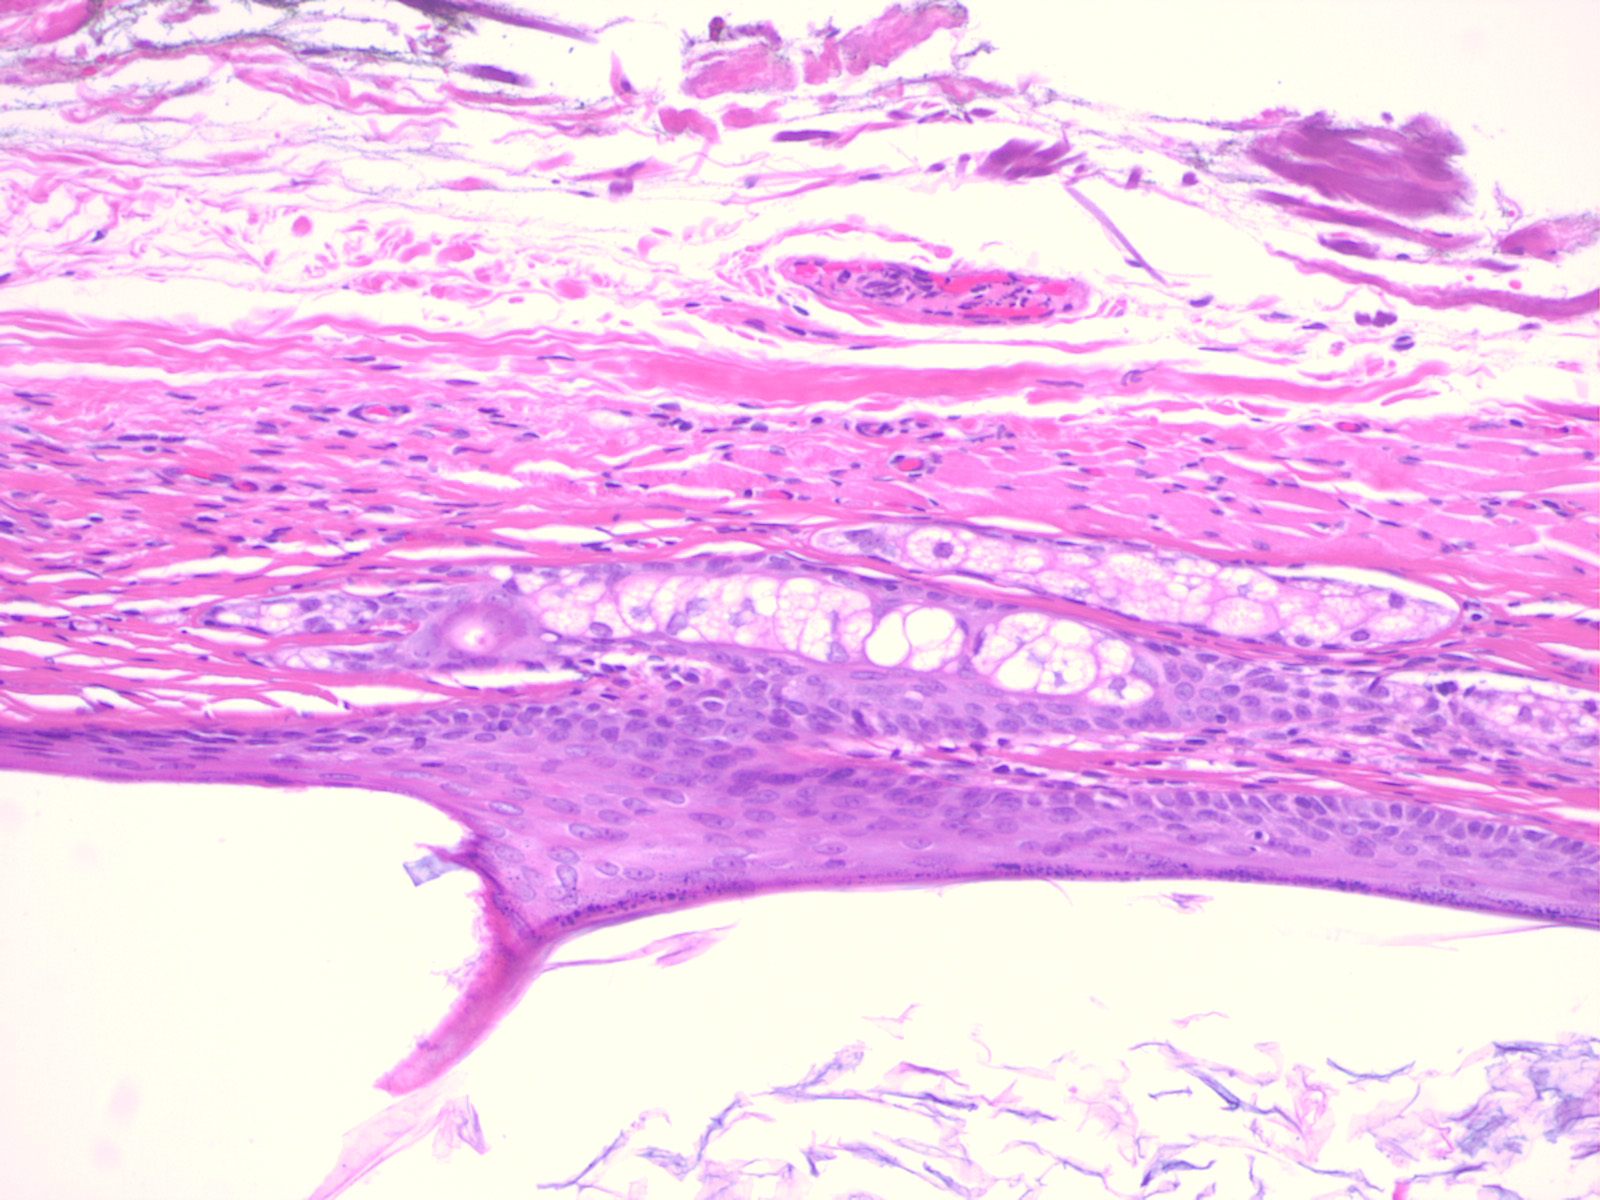

Histopathology. Dermoid cysts, in contrast to epidermal cysts, are lined by an epidermis that possesses various epidermal appendages that are usually fully matured . Hair follicles containing hairs that project into the lumen of the cyst are often present. In addition, the dermis of dermoid cysts usually contains sebaceous glands, often eccrine glands, ——–,. |